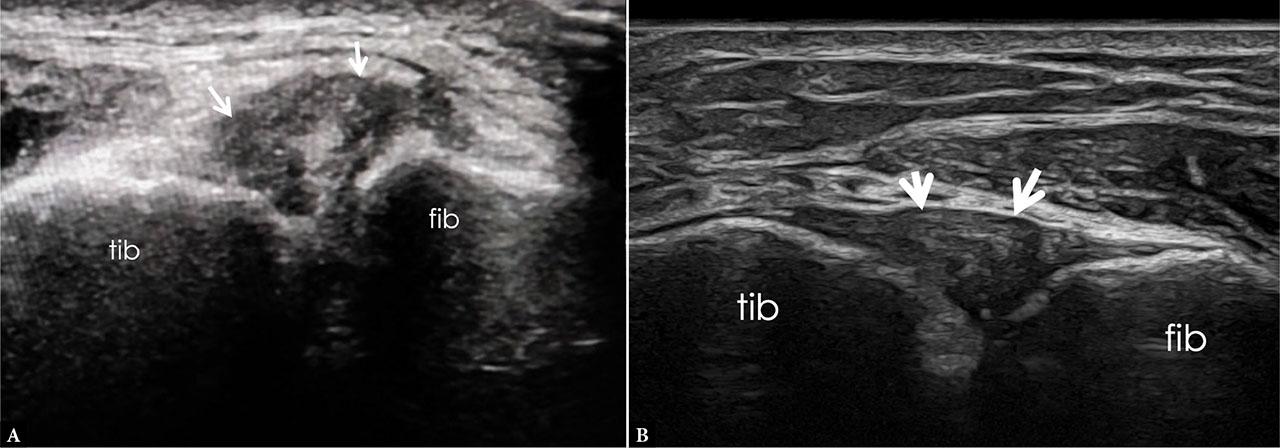

PiTFL: Best seen posteriorly, slightly deeper and thicker, extending between the posterior tibia and fibula (Fig. 4).

US image of the PiTFL obtained with a 20 MHz matrix linear probe. Ultrasound beam-steering was applied to orient the beam as perpendicular as possible to the PiTFL to reduce anisotropy artifacts (A). The ligament appears as continuous, fibrillar, hyperechoic band with defined margins (arrows), extending from the posterior aspect of the lateral malleolus to the posterior aspect of the tibia. The US linear probe is oriented obliquely at 35–45° from the posterior aspect of distal tibia to the lateral malleolus (B). CFL – calcaneofibular ligament; IoL – interosseous ligament